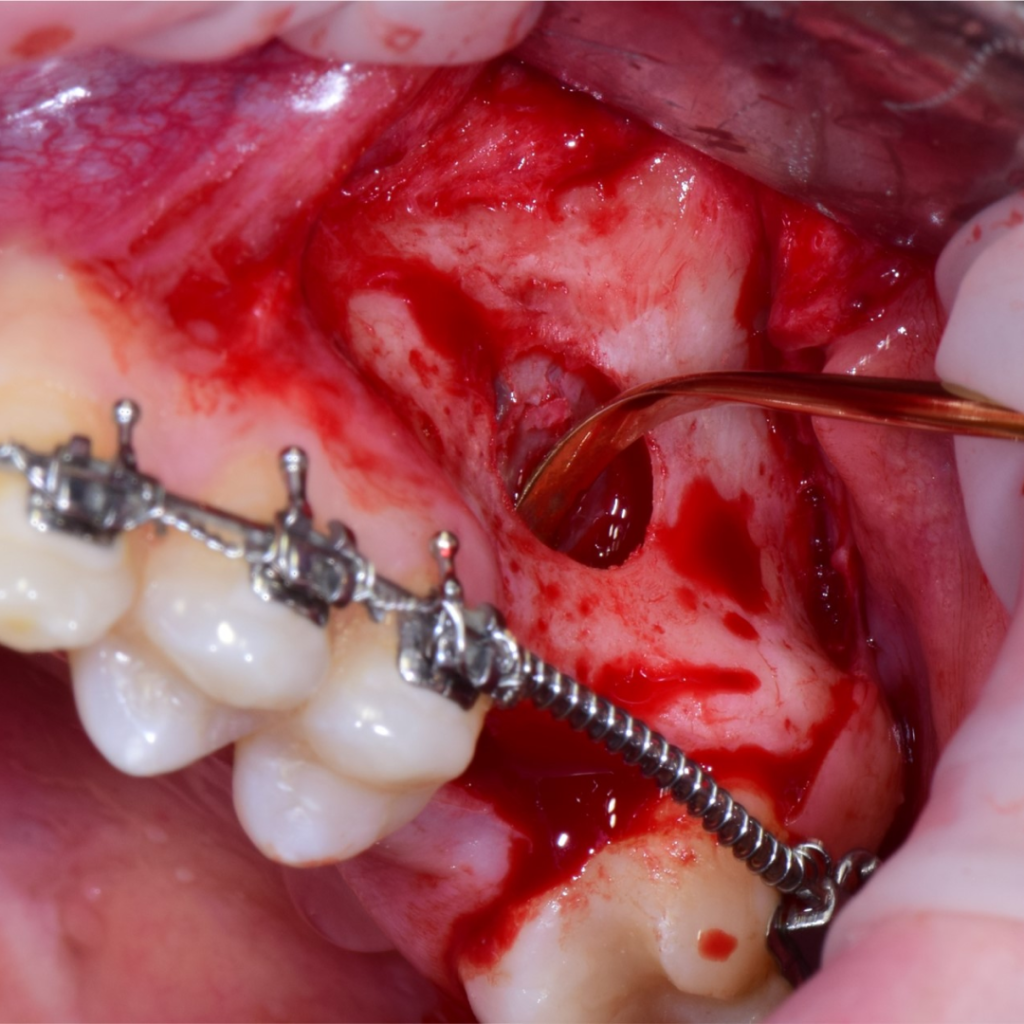

По результатам диагностики принято решение провести синус-лифтинг с помощью боров SinPro. В ходе вмешательства установлены имплантаты AnyRidge и AnyOne с первичной стабилизацией 40 Ncm.